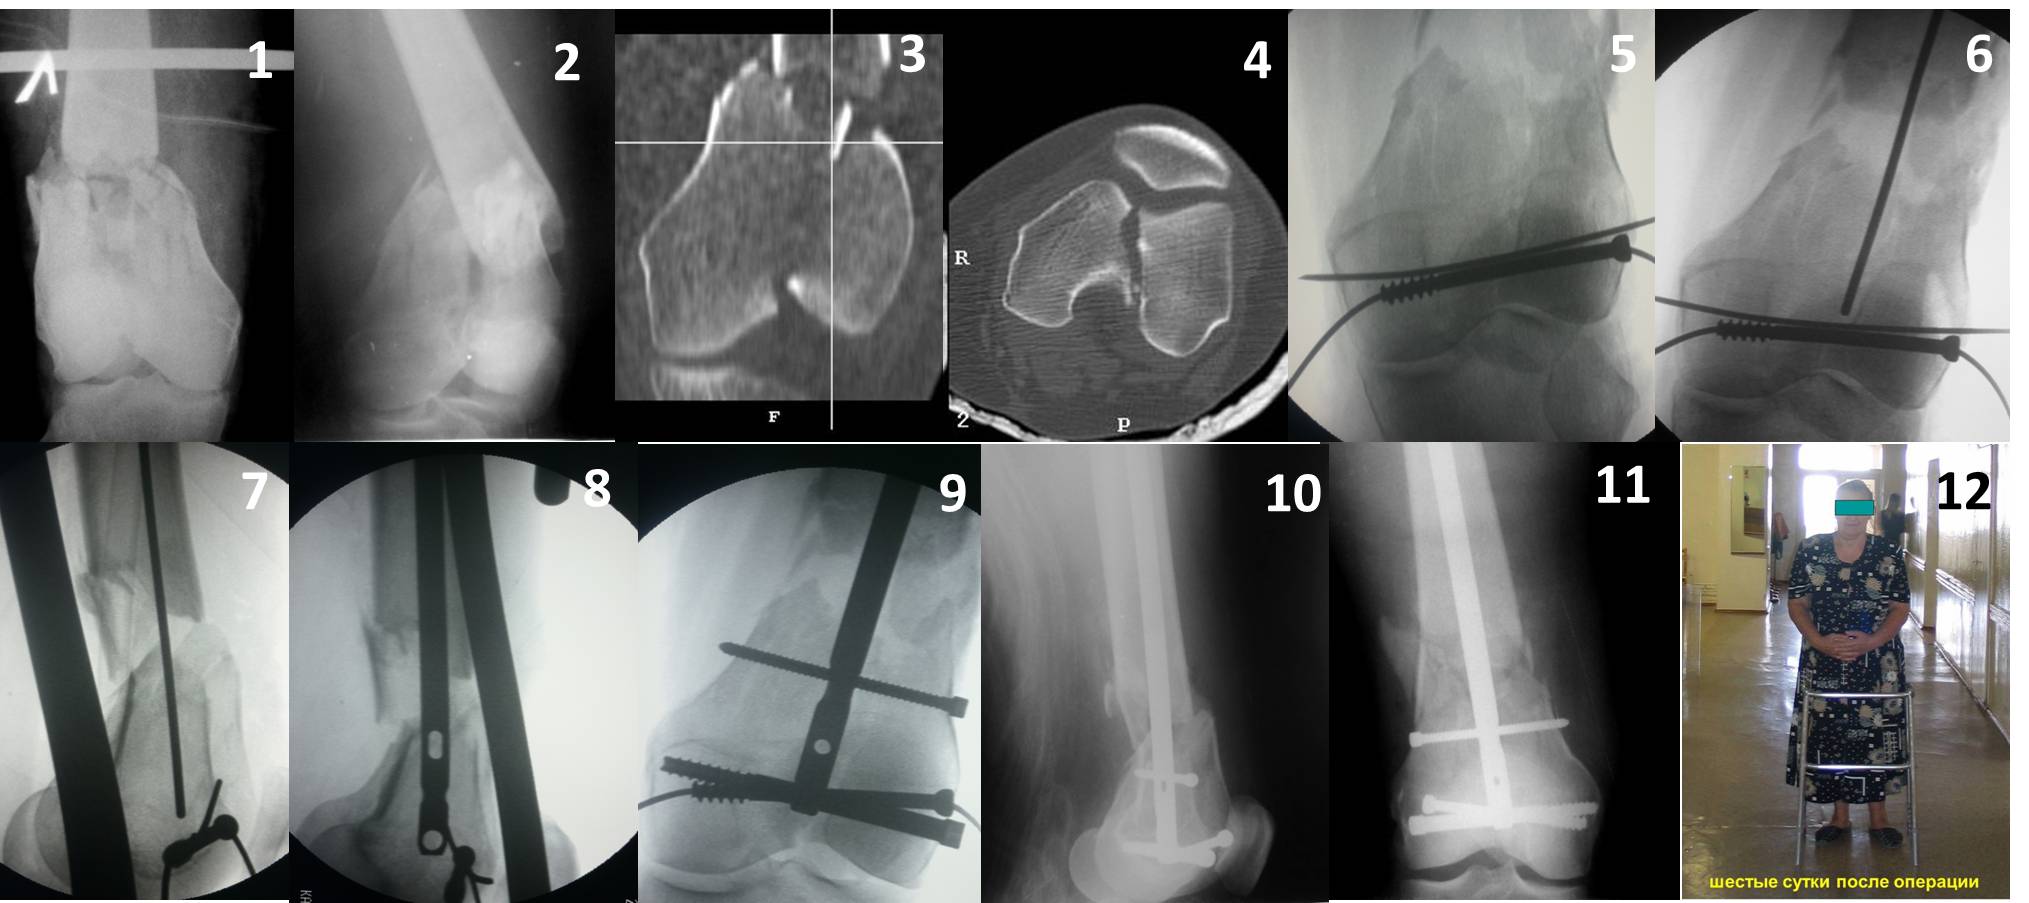

В приложении пример недавней операции, C3, открытая репозиция, фиксация мыщелков спицами и винтами, ретроградный синтез большеберцовым гвоздем 10,5 мм диаметром, винты 5 мм.

Позволю себе напомнить коллегам ещё раз, что являюсь сторонником антеградного остеосинтеза при переломах дистального эпиметафиза бедренной кости. Такая приверженность основана не на преимуществах внесуставного введения стержня или большем проценте положительных результатов. Она основана на возможности обеспечить блокирование на минимальном расстоянии от суставной поверхности в нескомпрометированной кости и, таким образом стабилизировать максимально низкие переломы. В приведенном Вами случае самый дистальный из блокирующих винтов проведен на расстоянии более 2 см от конца стержня. Из-за того, что к стержню присоединяется кондуктор, на стержне теряется 1-1,5 см его длины, где можно было разместить отверстия для блокирования. И что более важно, вместе с потерянной для этой цели длиной стержня утрачивается для размещения блокировочных винтов, пожалуй, самая ценная часть дистального эпиметафиза бедренной кости. Проблемы дистального блокирования в разных плоскостях, локализации точки ввода стержня при антеградном остеосинтезе – это всё решаемые технические проблемы. Но антеградный остеосинтез низких дистальных переломов бедра при адекватном блокировании в нескомпрометированной кости обеспечивает решение стратегической задачи – стабильный остеосинтез и возможность нагрузки.

Но практика показывает, что классификации существуют не зря, и стоит пользоваться ими, а не ориентироваться на абстрактные "максимально низкие переломы". Подавляющее большинство поступающих к нам больных с дистальными переломами - это C1 и С2. И показанный в прошлом сообщении гвоздик прекрасно справляется. Наверно, сгодятся и многие современные гвозди разных производителей, типа RAFN Synthes. А вот при настоящих C3 одним гвоздем не обойтись, нужны как минимум винты мимо, а то и введение на одном уровне нескольких винтов и/или спиц веером...

На этом большеберцовом стержне центр ближайшего к кондуктору отверстия в 14 мм от конца. И пример был про то, что пластина тут, скорее всего, была бы не худшим выбором.